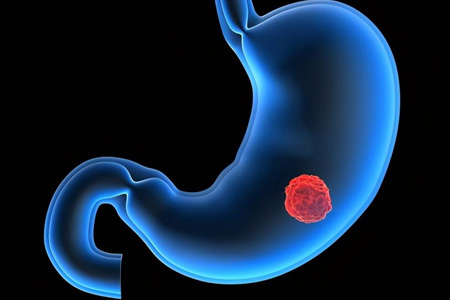

胃裏有腫瘤是什麽感覺?胃部腫瘤可能帶來的症狀和感受

胃部腫瘤是一種嚴重的疾病,它可能導緻許多不适和症狀。雖然腫瘤的确切存在通常需要醫療專業人士的檢查和診斷,但有些人可能會在早期出現一些特定的感受和症狀,提示胃内可能存在腫瘤。